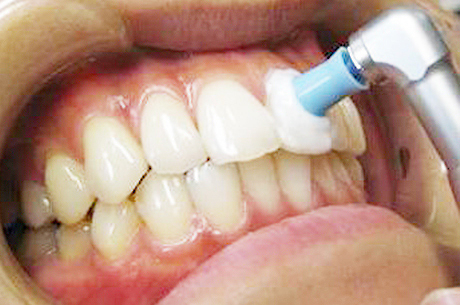

クリーニング

ひとりひとりに合わせた自費メインテナンス

今では広く歯科医院にて行われているPMTC(プロフェッショナル・メカニカル・トゥース・クリーニング)ですが、オリエント歯科はそれをPPC(パーソナライズド・プロフェッショナル・クリーニング)として再定義しました。